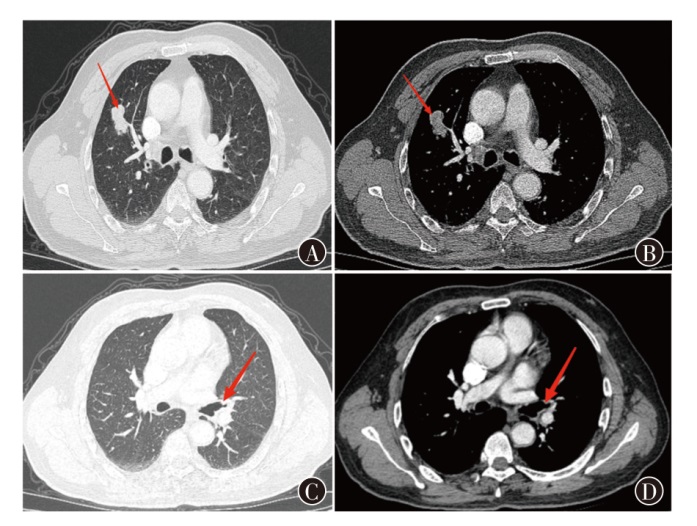

肺癌是我国发病率及死亡率最高的肿瘤性疾病之一,随着低剂量螺旋CT的广泛应用,早期肺癌的检出率逐年升高,双侧同时检出的病例也在逐渐增多,目前对于同期行袖式联合肺叶切除的病例研究较少,现报道1例单孔胸腔镜下左上肺舌段癌袖式切除同期行右肺上叶癌切除术患者的诊疗经过,并复习相关文献,供临床参考。